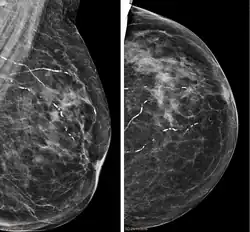

Right breast mammograms showing several calcified arterioles. Patient 94 years old.